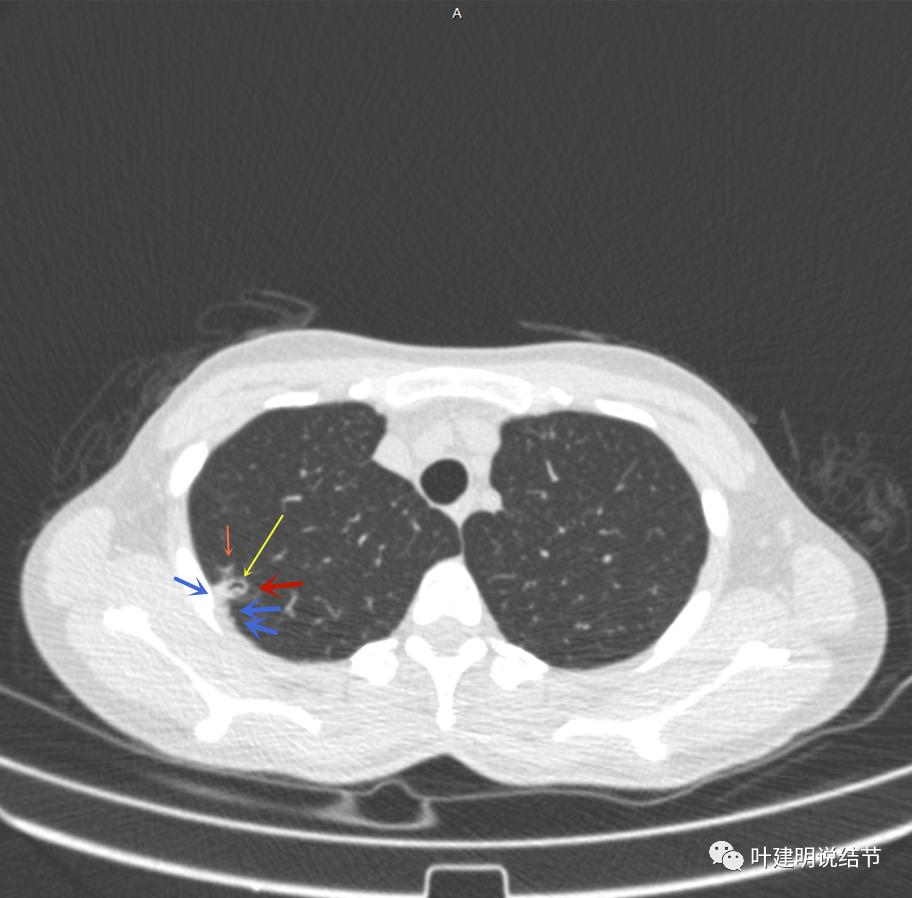

邻近胸膜有增厚(蓝色箭头),主病灶边界较清(红色箭头),实性部分密度过高(粉色箭头),旁边有磨玻璃影,散且模糊(砖色箭头)

邻近胸膜有增厚(蓝色箭头),主病灶实性部分密度过高(粉色箭头),旁边有磨玻璃影,散且模糊(砖色箭头)

邻近胸膜有增厚(蓝色箭头),主病灶实性部分密度过高(粉色箭头),旁边有磨玻璃影,散且模糊(砖色箭头),病灶有空腔(黄色箭头)